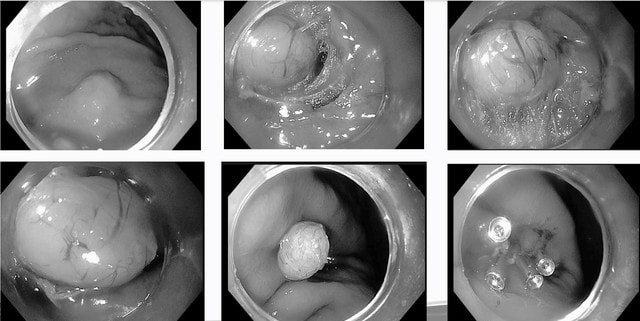

Bệnh nhân N.H.T. (61 tuổi, ở xã Vĩnh Tường, Nghệ An) vào viện trong tình trạng đau bụng, nôn. Các bác sĩ chỉ định chụp cắt lớp vi tính có tiêm thuốc và nội soi dạ dày. Qua nội soi, bác sĩ xác định đây là u dưới biểu mô dạ dày, kích thước khoảng 1,5 mm, xuất phát từ lớp cơ của dạ dày.

Các bác sĩ tiến hành rạch một đường niêm mạc ở vùng cách xa tổn thương (thông thường cách khối u khoảng 1–5 cm), sau đó đưa ống nội soi vào lớp dưới niêm mạc và di chuyển dần về vị trí khối u, tạo thành "đường hầm" để tiếp cận. Sử dụng kỹ thuật phẫu tích cắt dưới niêm mạc (ESD) để cắt bỏ toàn bộ khối u một cách chính xác. Sau khi đã cắt bỏ hoàn toàn khối u, bác sĩ tiến hành đóng đường rạch niêm mạc bằng clip.

Theo ThS.BS Lưu Tuấn Anh – khoa Nội Tiêu hóa, Bệnh viện Hữu nghị Đa khoa Nghệ An, người trực tiếp thực hiện kỹ thuật nội soi can thiệp cho bệnh nhân – cho biết: "Kỹ thuật STER (Submucosal Tunneling Endoscopic Resection) được xem là bước tiến trong nội soi can thiệp. Bác sĩ tạo một 'đường hầm' nhỏ trong lớp dưới niêm mạc, tiếp cận trực tiếp khối u để bóc tách và lấy ra ngoài mà không phải cắt bỏ một phần dạ dày."